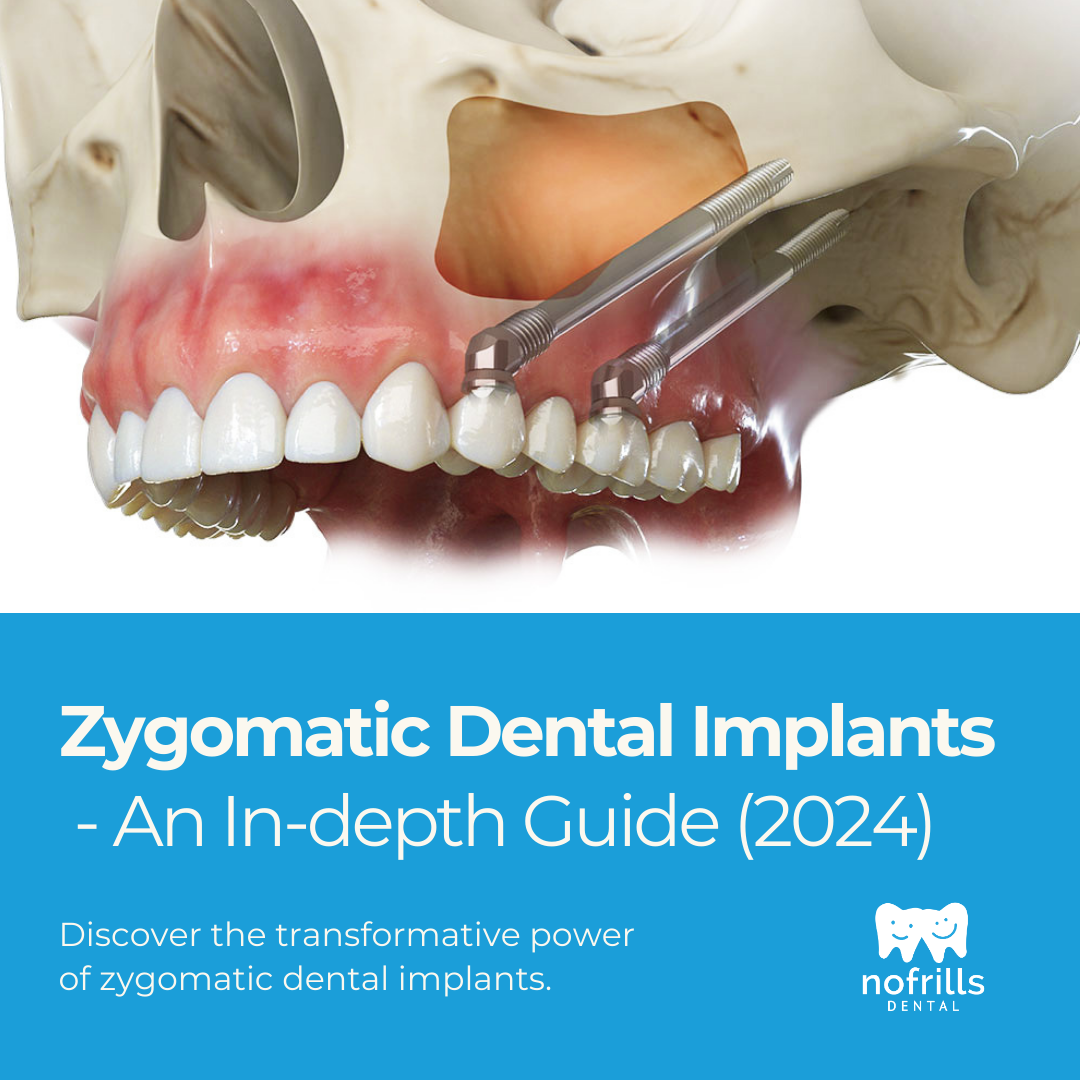

Zygomatic Dental Implants: An In-depth Guide

Zygomatic dental implants represent a revolutionary advancement in the field of dental implant surgery, providing a viable solution for individuals wi…